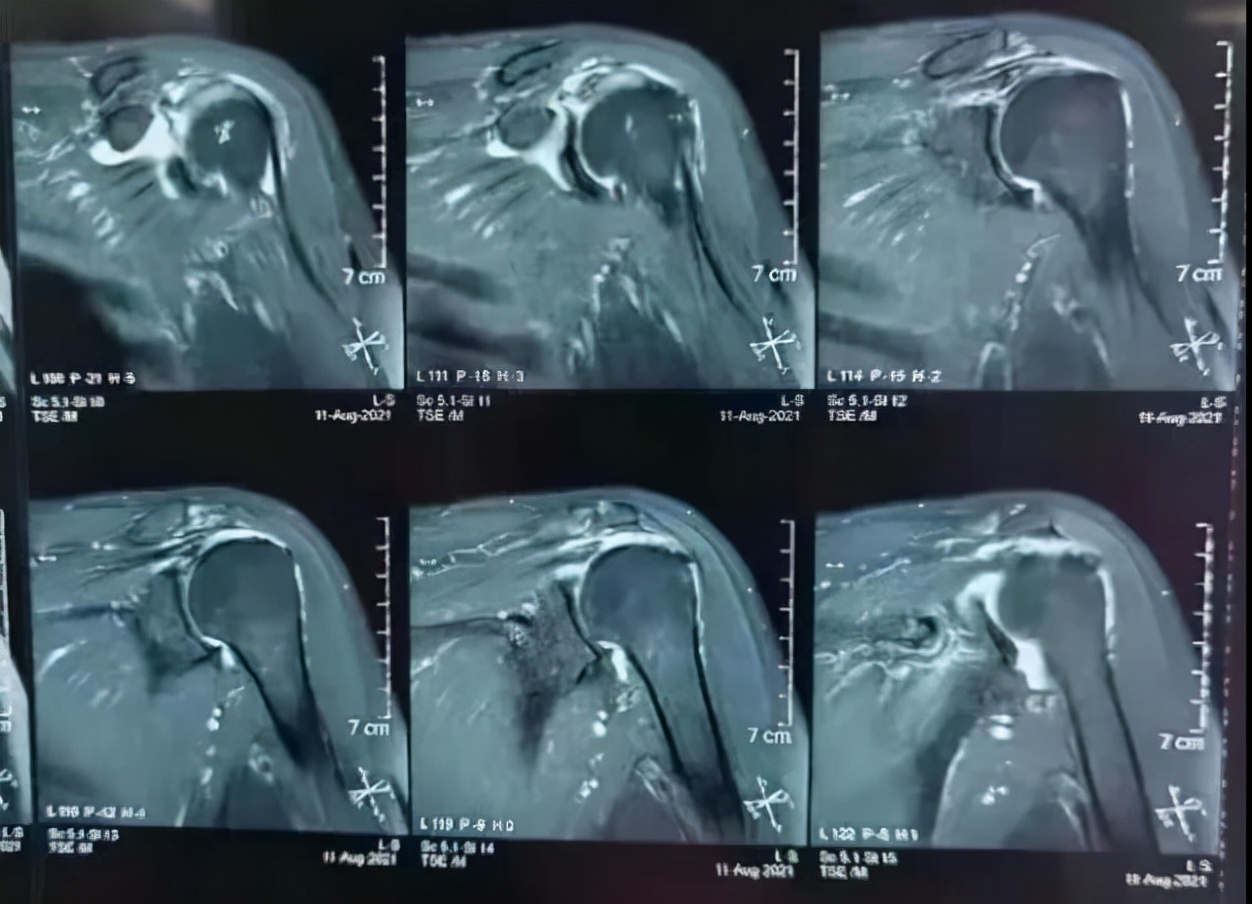

近日,沈阳医学院附属中心医院运动医学科(骨外二科)收治了一位老年女性患者,摔伤后左肩部疼痛、活动受限6天,于外院行左肩关节磁共振显示左肩袖撕裂,患者及家属辗转多家医院,口服止疼药物、中医理疗等对症治疗一段时间后,肩部疼痛未见缓解。患者经过多方打听来到了骨外二科。骨外二科主任、运动医学专家阿良详细询问病史、查体及阅片后明确诊断为:不可修复巨大肩袖撕裂(冈上肌、冈下肌及肩胛下肌撕裂)。顾名思义肩袖是由4根筋组成的,其中的3根筋已经完全断裂。虽然病情严重,但听到主任阿良介绍微创手术可以治疗,患者的心中充满了希望!

左肩关节MRI显示